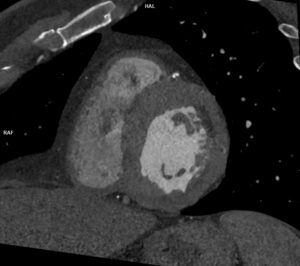

Figurile 2, 3 și 4: reconstrucţii oblic coronale aortă postoperator